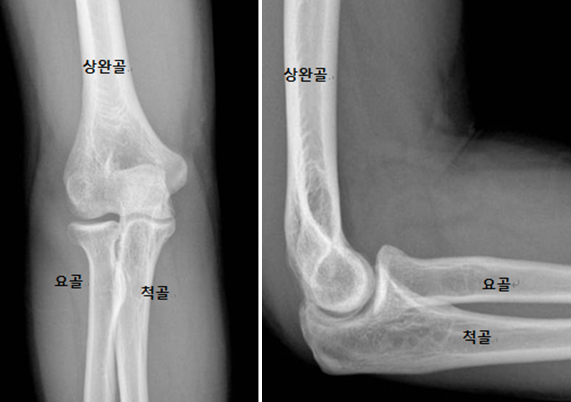

팔꿈치는 상완과 전완을 연결하는 복잡한 관절로 위팔의 상완골, 팔뚝의 척골 및 요골의 3개 뼈로 구성된 복잡한 경첩 관절로 우리 몸에서 중요한 역할을 합니다. 인대, 힘줄, 근육이 관절을 지지하여 다양한 움직임을 가능하게 하며, 일상생활의 다양한 활동에서 중요한 역할을 합니다.

팔꿈치 관절은 세 개의 주요 뼈로 구성되어 있습니다: 상완골 (upper arm bone), 요골 (forearm's radius bone), 그리고 척골 (forearm's ulna bone). 이 세 뼈는 팔꿈치의 기본적인 구조를 형성하며, 각각 다른 기능을 가지고 있습니다.

- 상완골 (Humerus): 상완골은 어깨와 팔꿈치 사이의 상완에 위치한 긴 뼈입니다. 이 뼈의 하단은 팔꿈치 관절의 일부를 형성하는 두 개의 돌출부, 즉 외측과 내측 상과돌기를 가지고 있습니다.

- 척골 (Ulna): 척골은 전완의 내측에 위치한 뼈로, 팔꿈치의 주된 힌지 기능을 담당합니다. 이 뼈의 상단에는 팔꿈치를 구성하는 중요한 구조인 척골 돌기가 있습니다.

- 요골 (Radius): 요골은 전완의 외측에 위치한 뼈로, 팔의 회전 운동을 가능하게 합니다. 요골 머리는 팔꿈치 관절 내에서 척골과 상호 작용합니다.